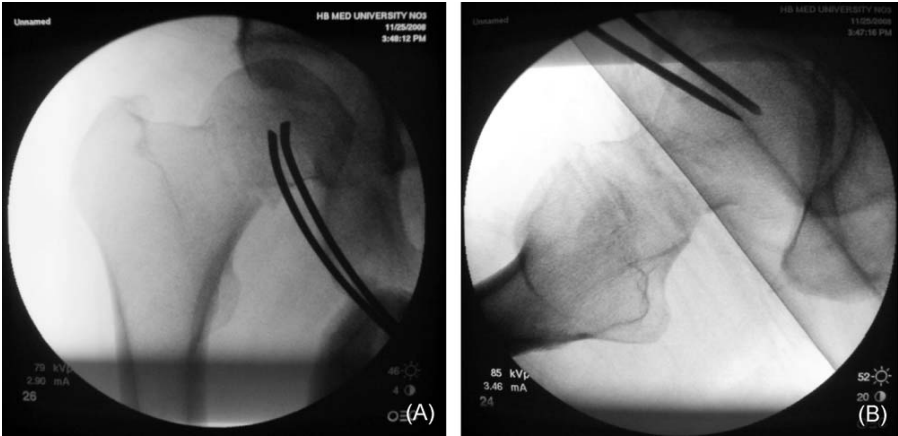

或者,更罕见的是,近端节段旋转后嵌插入远端部分,并作为一个整体随远端部分移动。结果,移位-嵌插型股骨颈骨折无法通过手法操作复位(图2)。

图 2. 一名54岁女性从约1.5米高处坠落导致的难复性右股骨颈骨折。远端节段嵌插入近端部分并随之旋转,脱位的股骨头无法通过手法操作复位(A,前后位X光片;B,右股骨颈骨折的CT三维重建图像)。